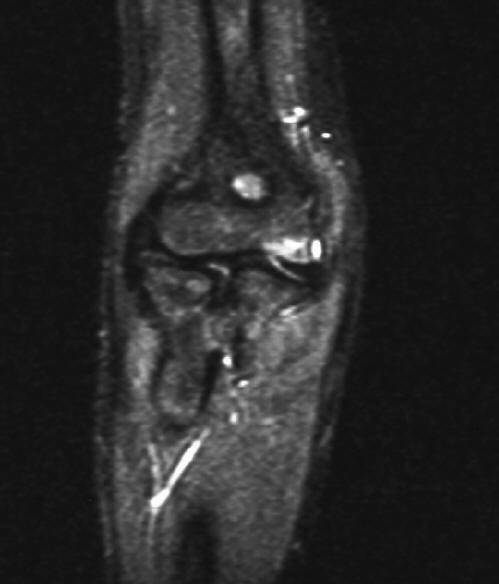

下面这是一个比较极端的例子,120 天的陈旧儿童桡骨颈骨折切开复位,同样获得满意的结果。

2 年后的 X 线片

2 年后 MRI 未发现桡骨头坏死